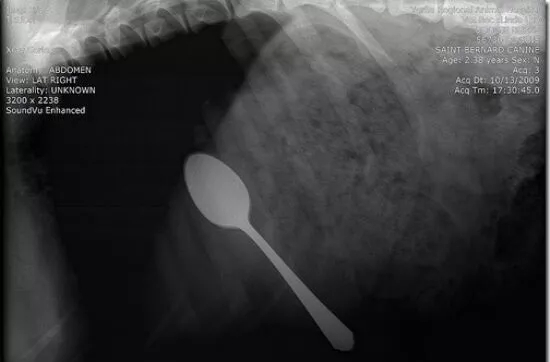

这是什么?刀吗?我的天啊!

这些都是在狗狗的胃里发现的,拍的X光图,看到那把刀在狗狗胃里,心里不紧张吗不担心 ,万一你家的狗狗也吃下去,想都不敢想!

狗狗似乎总是无法控制自己去吃一些没有营养价值的东西。针线、木勺、硬果壳、果核、塑料袋、珠宝、石块、抹布和袜子都有可能吃下去,狗狗胃内长期滞留这些异物不能被胃液消化,会造成胃黏膜损伤,影响胃功能。